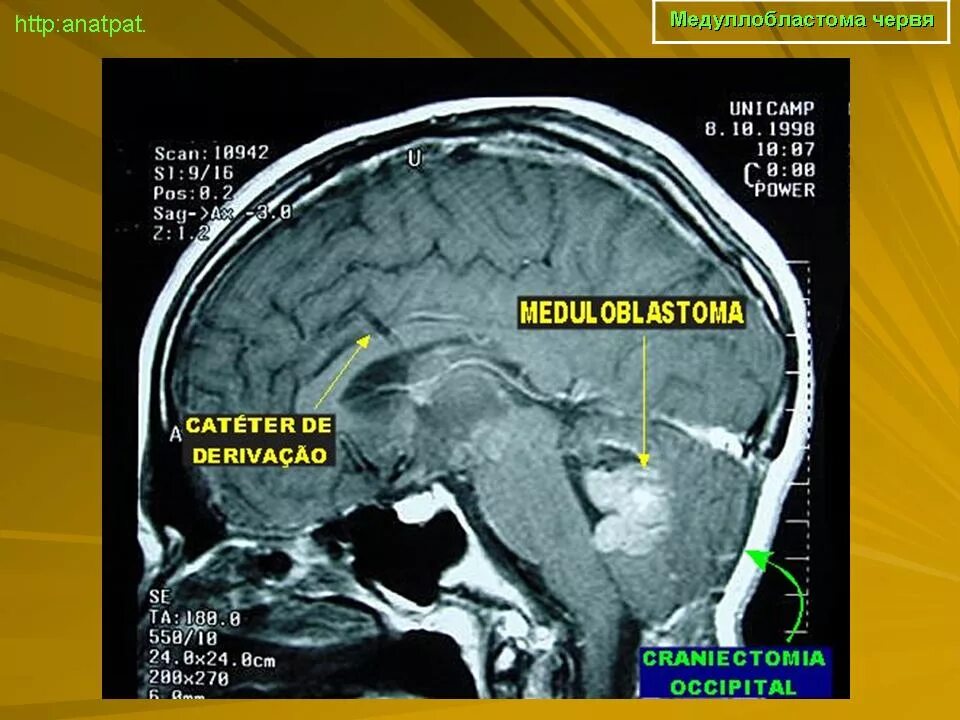

Медуллобластома это